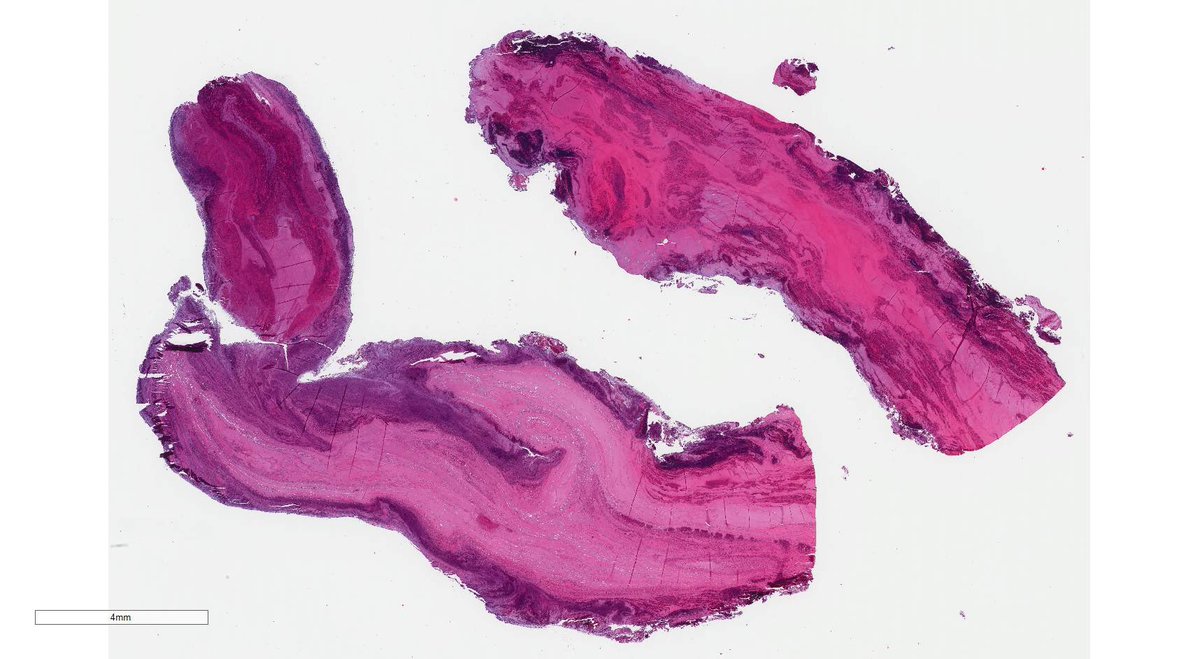

Bag of worms. Hydrophilic polymer embolisation with secondary thrombosis. This is a thrombectomy specimen from the right femoral artery in a patient undergoing peripheral vascular surgery. The guidewires are coated in this material that can occasionally embolize. Yikes!